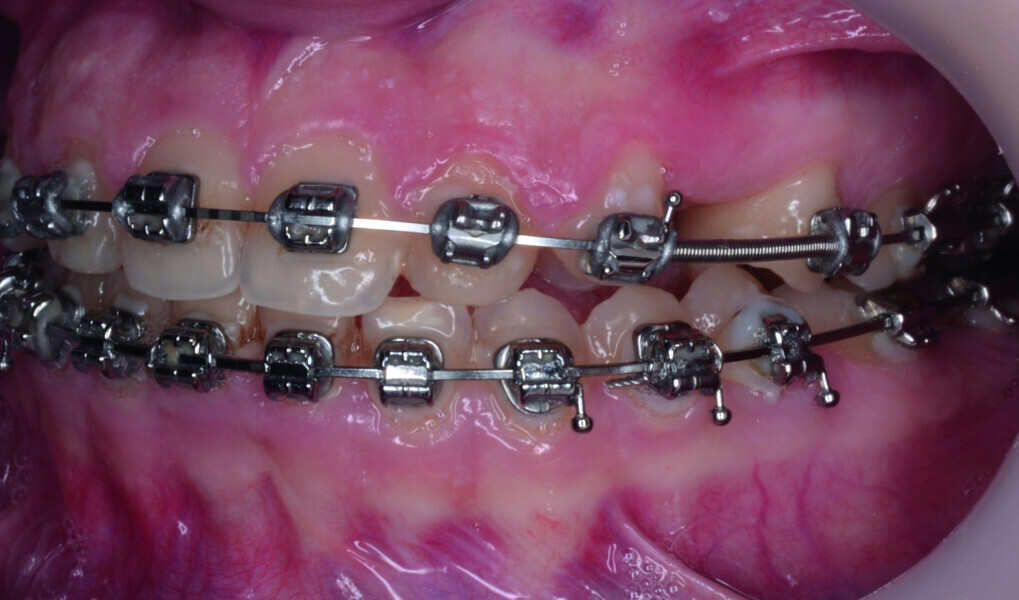

Orthodontic management of maxillary lateral incisors agenesis